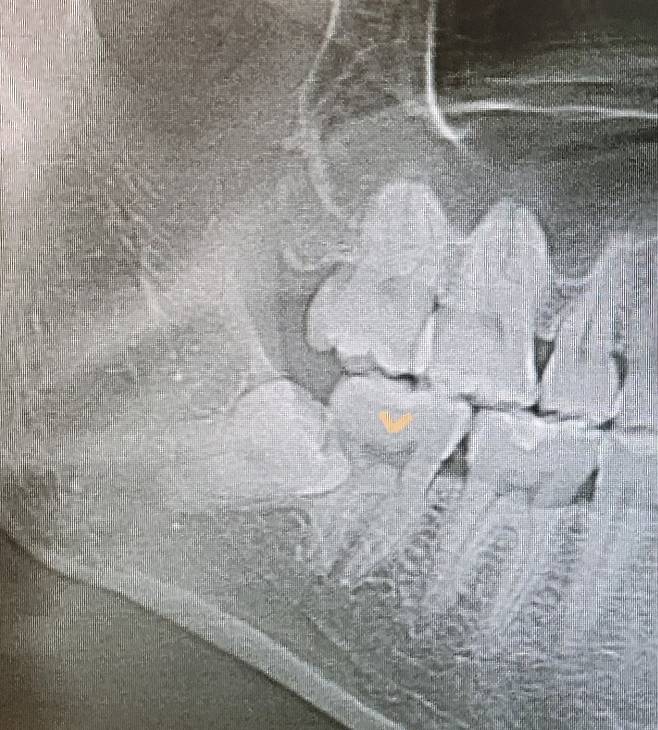

ct찍어보니까 사랑니가 신경에 걸쳐있다고 발치하지말라고 합니다

유명한 사랑니 발치 전문치과인데도 불편한거 없으면 뽑지말고 놔두라고 합니다

신경 손상 우려가 매우 심하다고 손 못댄다고 하네요

살짝 틈이 있어서 음식물 끼는건 치간칫솔 넣어서 꺼내면서 양치합니다

의사선생님 말 듣는게 맞겠죠?